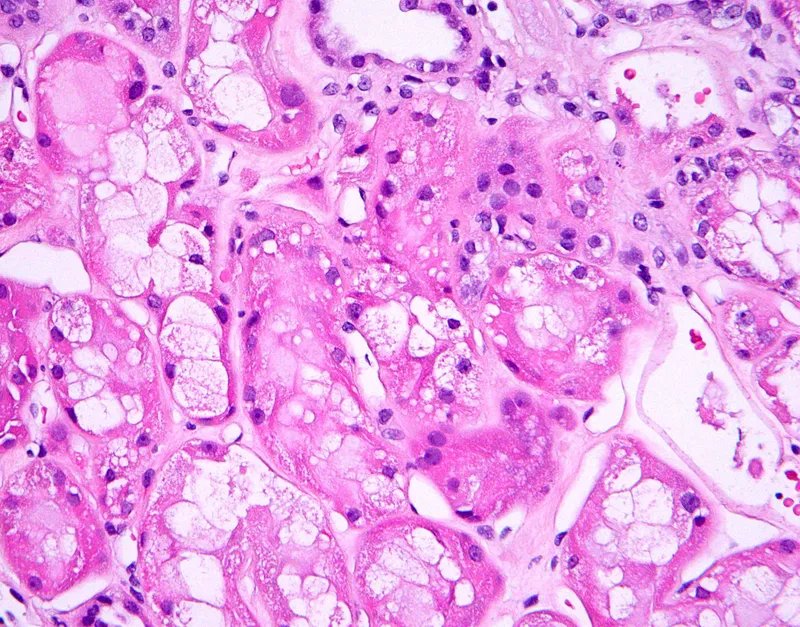

Morphology - Muddy Brown Mayhem

- Microscopy:

- Tubular Injury: Necrosis and sloughing of proximal tubular epithelial cells, with loss of brush border and tubular dilation. The basement membrane is typically spared.

- Casts: Pathognomonic muddy brown granular casts in distal tubules and collecting ducts.

- Interstitial edema.